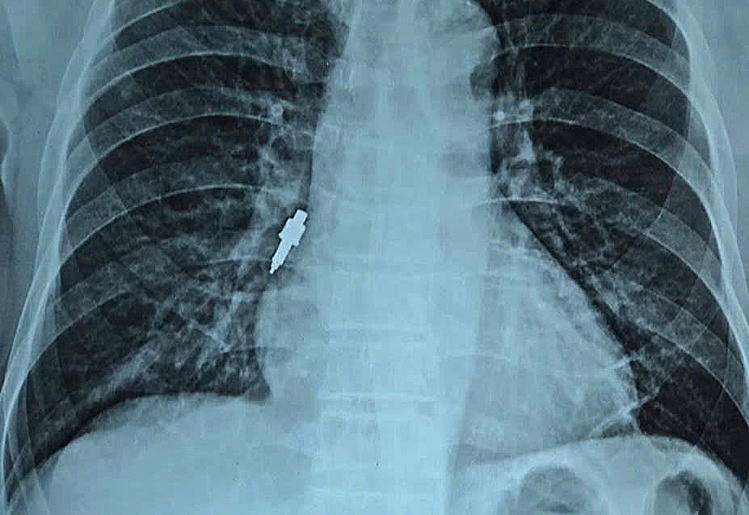

Metal foreign body deeply lodged in the airway. Photo: Supplied by Hospital |

On 26/11, doctors at Huu Nghi Hospital successfully removed a foreign body via endoscopy. The object, a smooth, stainless steel dental tool, measured 2,5 cm long with a maximum diameter of 1 cm, was deeply lodged in the patient's right bronchus.